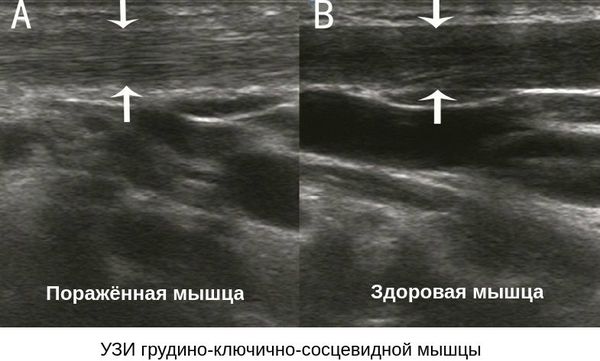

Для уточнения вида кривошеи и ее причины малышу может потребоваться ультразвуковое исследование или рентгенография шейного отдела. На дополнительную диагностику, если она будет необходима, направит врач – после того как осмотрит ребенка, прощупает здоровую и пораженную мышцу.

Дополнительно по назначению ортопеда проводится комплексное исследование позвоночника — УЗИ мышц шеи и рентгенограмма шейного отдела позвоночника. Проведение МРТ и электромиографии не показано для детей младшего возраста, так как эти исследования требуют определённой подготовки ребёнка.